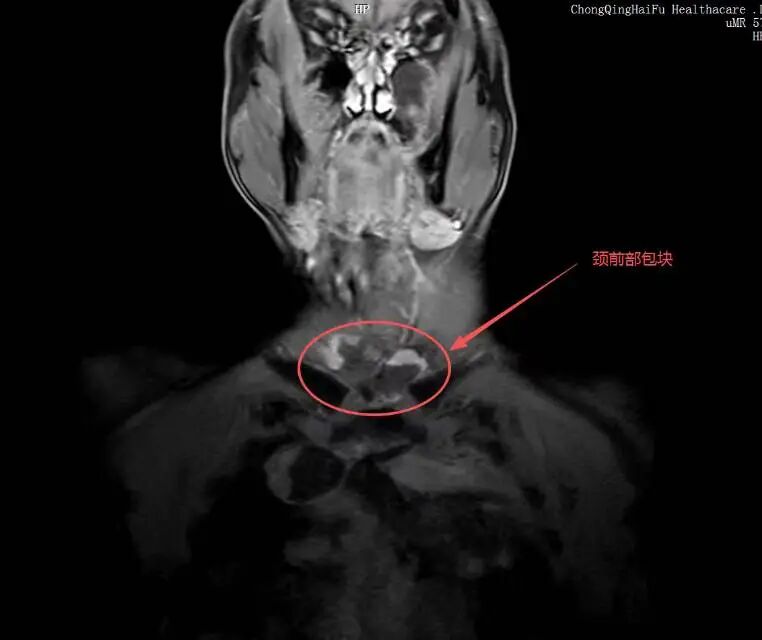

复查 MRI 显示肿瘤消融范围理想,病灶无灌注区清晰可见,远超预期。手术过程十分顺利,术后患者生命体征平稳,术后第一天,患者疼痛就明显缓解,精神、饮食都恢复良好。